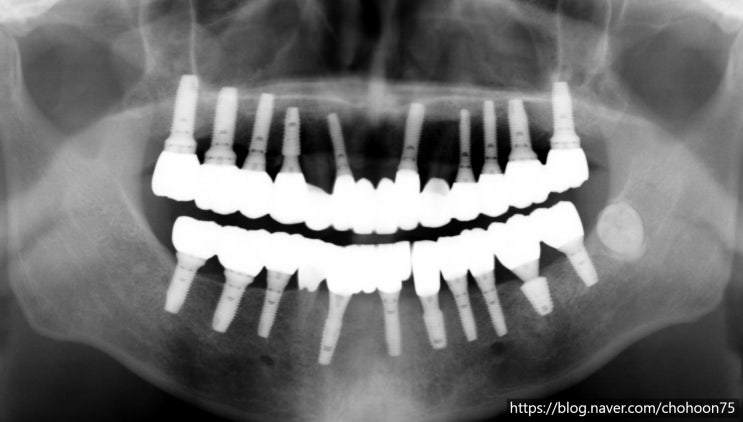

안녕하세요. 조훈 치과입니다. 구치부는 저작 활동을 담당하며 전체 교합을 지탱하는 핵심 역할을 하고 앞...